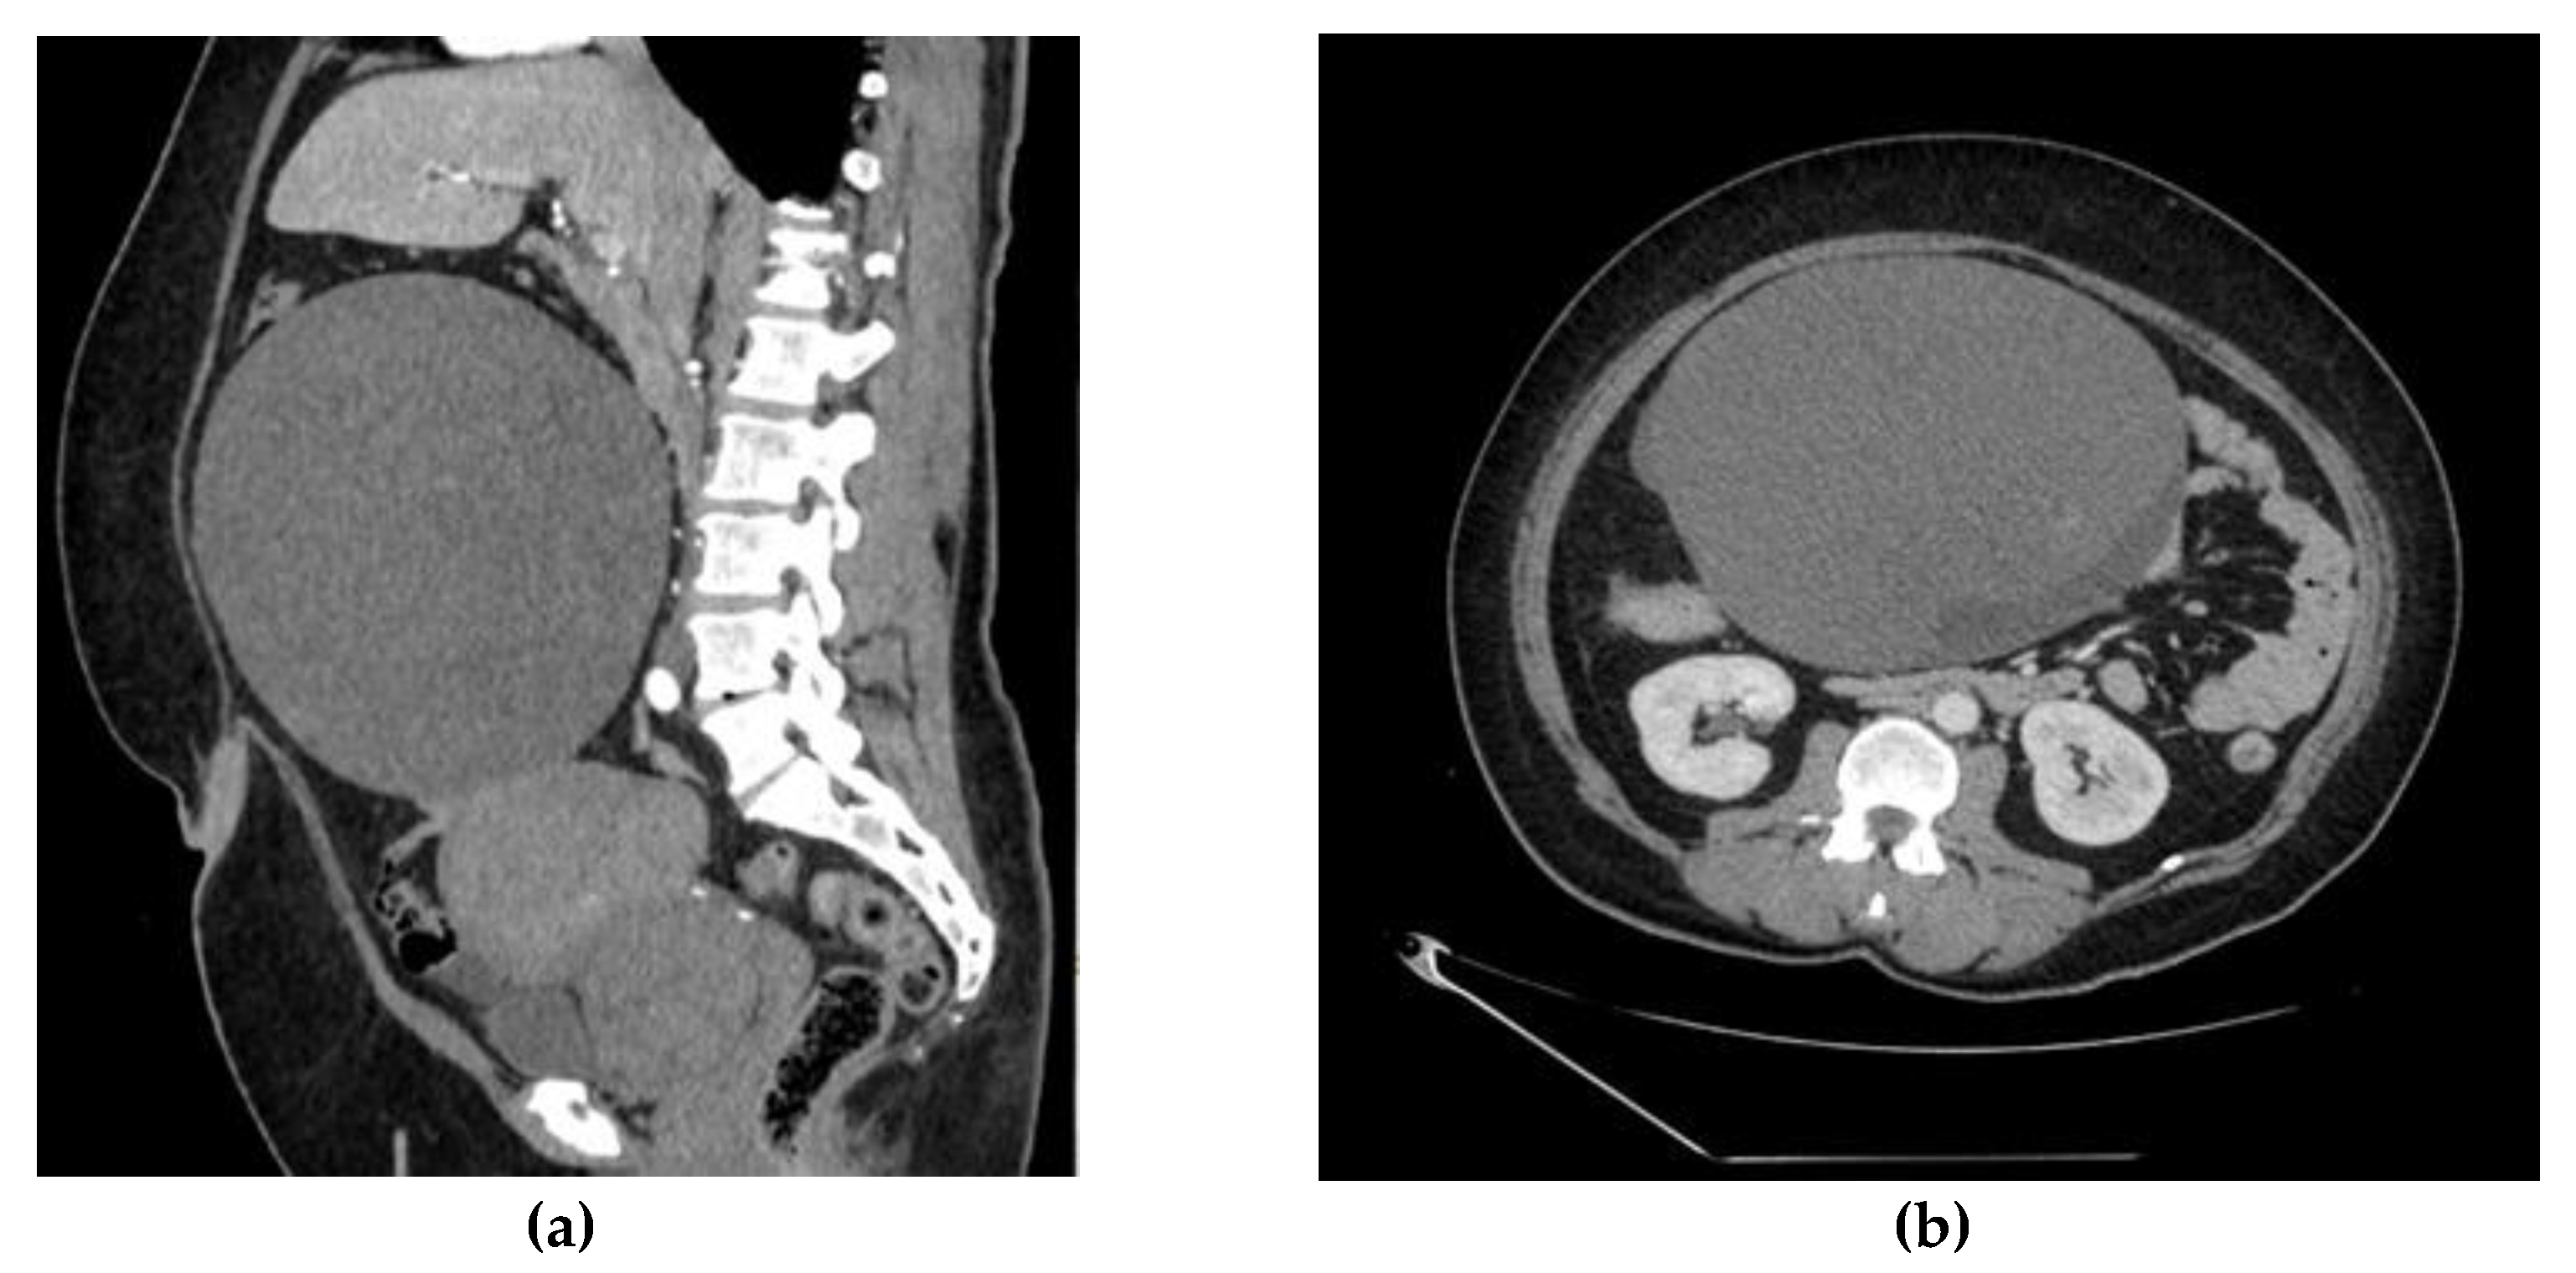

2. Case Report